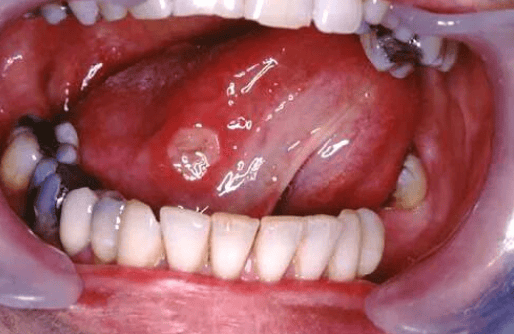

口腔溃疡是白塞氏病最常见的首发症状,约95%的患者会出现反复发作、疼痛明显的口腔溃疡。这些溃疡通常出现在颊黏膜、舌头和牙龈上,大小不一,可能持续数周才愈合。与普通溃疡不同,白塞氏病相关的溃疡往往更频繁、更严重,且愈合后容易复发。如果患者每年有三次以上反复发作的口腔溃疡,并伴随其他症状,应高度警惕白塞氏病的可能性。